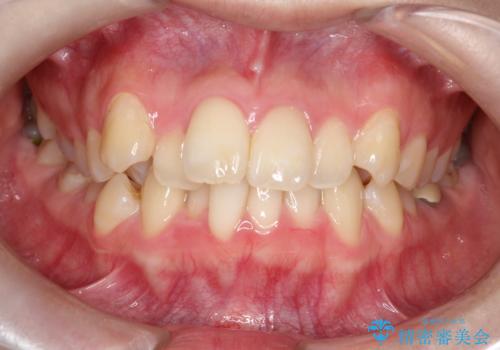

- 「歯のデコボコと前歯が引っ込んでいるのを治したい」を主訴に来院された患者様です。

デコボコの量が多かったため上下左右4を抜歯してワイヤー矯正で治療を行いました。

正面から見たときに右上2が全く見えないくらい、右上2が後ろに引っ込んでいる状態でしたが綺麗に並べる事が出来ました。

笑った時のスマイルラインもかなり綺麗になり大変ご満足いただく事が出来ました。